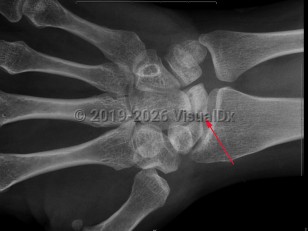

Avascular necrosis (osteonecrosis) is characterized by tissue death due to reduction or loss of blood supply to a bone. Causes include joint or bone trauma, fatty deposits in blood vessels, corticosteroid use, alcohol abuse, and some diseases. Other risk factors are chemotherapy, radiation therapy, and organ transplantation. May occur at any age, but most commonly occurs in adults aged 30-60. Patients are typically asymptomatic early on, but most experience joint pain increasing in severity as the disease develops. The femoral head site is most commonly affected, but the humeral head site, femoral condyles, and small bones are also sites of common occurrence. Typically, clinical presentation consists of sudden onset of pain in the joint.